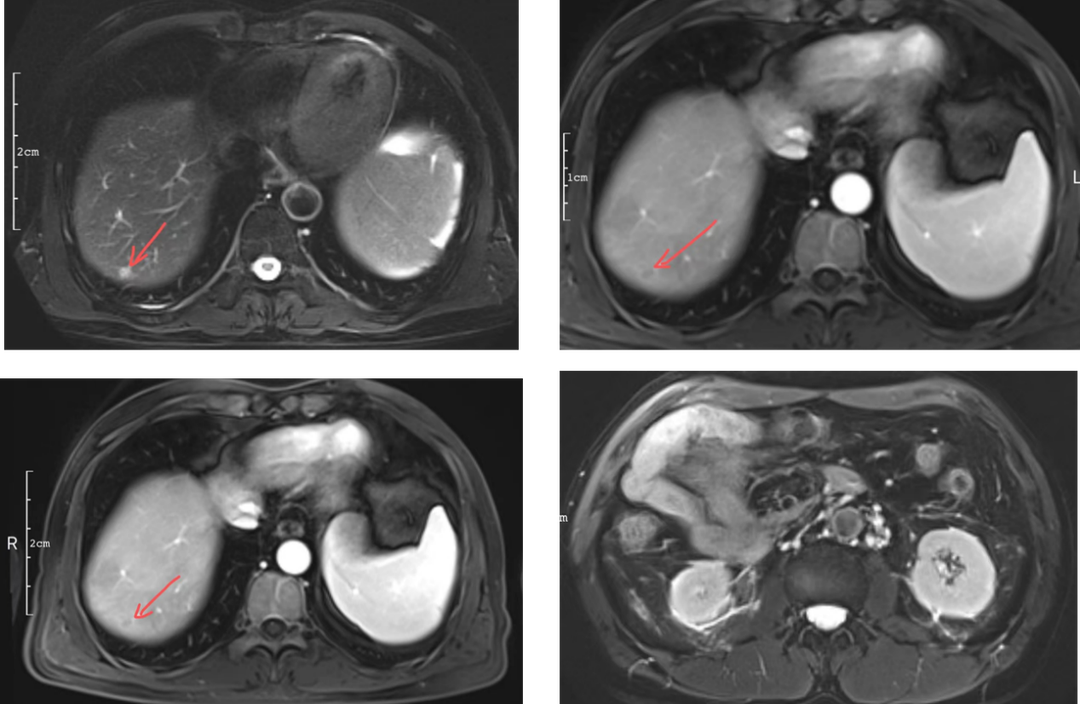

在全球,结直肠癌是发病率位居第三位、病死率位居第二位的肿瘤。肠镜筛查的普及以及手术方式的提升显著降低了结直肠癌的死亡率,但仍有一部分患者在初诊时已发展为晚期,失去手术根治的机会,且预后较差,5年生存率仅12%。许多转移性结直肠癌(mCRC)患者在经历一线治疗后,面临无药可用的困境。近年来,随着靶免联合治疗在系统治疗中逐渐前移,各种靶向治疗药物在mCRC的诊疗中也越发举足轻重。本文分享2例晚期结肠癌患者的诊疗经过,呈现瑞戈非尼在二线治疗为患者带来长生存的治疗价值及其良好的后线应用前景,以期为临床医生提供诊疗借鉴。 病例提供:海军军医大学附属长征医院 王湛 王湛 病例基本情况 一般信息:女 ,58岁。2020年10月,患者无明显诱因出现腹胀,无伴随症状,未予重视。后腹胀进行性加重,2020年11月中旬下腹部隐痛,与进食及体位变化无关,无肩背部放射痛。 辅助检查: 腹部超声:腹腔积液。 腹水脱落细胞病理:腺癌。 腹部增强CT:结肠肝曲癌;腹盆腔积液,腹盆腔腹膜多发转移。 结肠镜(2020-12-4):升结肠近肝曲见隆起型新生物,范围约4cm,新生物表面分叶状,质脆,触之易出血。肠腔狭窄,内镜尚可通过。 2020-12-8病理:横结肠,中分化腺癌,含部分粘液腺癌。 一线治疗2020-12-03至2021-02-24 CAPEOX+贝伐珠单抗 治疗4周期 病情进展,腹胀、腹痛加重,腹水增加。 2021-3-31 PET-CT:腹腔内及腹膜、脾脏、纵隔及右侧心膈角区、左侧锁骨区多发代谢增高灶,结合病史,考虑转移;双肺转移;腹腔及盆腔积液;结肠显示欠清,请结合肠镜检查;双侧胸腔少量积液,左肺下叶部分不张;双肺少许慢性炎症;右肝血管瘤;左肾结石。;子宫术后,痔疮可能;脊柱退变,腰3不稳,腰3/4、4/5、腰5/骶1椎间盘突出。 PFS:3个月 2021-4-6,完善基因检测(腹水标本):KRAS/APC/TERT/TP53/ target=_blank class=infotextkey>P53 突变,TMB 7.98/Mb,MSS 二线治疗,2021-04-02至2021-12 2021-3-31 2021-6-2 2021-8-6肠镜:结肠镜顺利插至回盲部,回盲瓣呈唇状。结直肠粘膜呈桔红色,光滑湿润,有光泽。血管纹理呈树枝状,清晰可见。 PFS:8月 三线治疗,2021-12-13至2022-01-23 三氧化二砷 2021-6-2 2021-11-22 2021-11-22 2022-2-8 PFS:2月 四线治疗,2022-02-10 化疗+免疫+瑞戈非尼+三氧化二砷 2022-2-10开始使用小剂量化疗(雷替曲塞+奥沙利铂+伊立替康)+免疫(信迪利单抗)+瑞戈非尼+三氧化二砷治疗。 疗效评估(2022-9-20):患者病情再次取得缓解。 2022-9-22至今采用维持治疗,降低治疗强度:雷替曲塞 +信迪利单抗+瑞戈非尼+三氧化二砷 2022-9-20 2023-2-8 PFS:13个月+ 该患者为中年女性,诊断为晚期多发转移性结肠癌,基因检测提示KRAS突变,BRAF、NRAS野生型,微卫星稳定,无法进行根治性切除。一线治疗加予CAPEOX联合贝伐珠单抗,治疗4周期后出现病情进展,腹胀、腹痛加重,腹腔积液增加,二线采用瑞戈非尼联合免疫和化疗,患者耐受良好,1周期后腹胀明显缓解,全身状态、PET-CT、肠镜结果较之前明显改善,继续原方案治疗,PFS长达8月。二线治疗进展后完善基因检测,发现TP53 突变,经与患者充分沟通,三线治疗采用三氧化二砷,疗效不佳。四线治疗在三氧化二砷基础上加用瑞戈非尼+免疫+化疗,患者病情再次取得缓解,PFS 超过13个月。近年来,随着精准医学及靶向、免疫治疗的发展,mCRC的管理与治疗策略的制定也变得复杂,合理选择治疗手段、优化全程管理至关重要。本例患者经历了一线化疗联合免疫治疗后疾病出现快速进展,我们个体化地在二线治疗中应用瑞戈非尼联合方案,患者疾病得到控制,PFS 8个月。在四线治疗方案中,再次挑战瑞戈非尼,依然获得较好的疾病控制效果,目前PFS已超过13个月。基于CORRECT和CONCUR研究,瑞戈非尼用于mCRC三线治疗已积累大量临床数据,目前已成为mCRC三线标准治疗方案。此外,REGONIVO、REGOTORI以及RIN方案证实了瑞戈非尼联合免疫治疗MSS型肠癌取得更长的总生存期。一线治疗后疾病进展,能否将瑞戈非尼使用前移,在二线治疗中加用以进一步延长患者生存,以及前线已经暴露过瑞戈非尼,后线再次使用瑞戈非尼是否可行,仍待在临床研究中进一步证实。 02 病例分享二 病例提供:海军军医大学第一附属医院 王薇 王薇 病例基本情况 一般信息:男性,41岁。2020年10月8日,无明显诱因下出现便血,为鲜红色,伴肛门坠胀不适,无排便习惯改变,无腹胀,无消瘦。1997年因“胃溃疡”行胃部幽门切除术;2019年行混合痔手术。 辅助检查: CEA 3.4ng/ml,CA199 3.52u/ml。 当地医院肠镜(2020-11-20):(距肛缘8-10cm)可见粘膜不规则隆起,表面溃烂,易出血。 肠镜活检病理:(直肠)中分化腺癌。 盆腔MRI增强(2020-11-26):直肠中段癌,考虑mrT3N1Mx,MRF-,EMVI-。 肝脏MRI增强(2020-11-27):未见明显异常。 治疗经过 首次手术治疗2020-12-09 腹腔镜辅助直肠癌拖出式适形切除术+末端回肠造口术 术中探查:直肠下段肿物,质硬,未浸润浆膜层,周围系膜未见肿大淋巴结。肿瘤大小约4*4*2cm,占肠腔1/2周,系膜完整。 术后病理: 直肠溃疡型肿瘤大小4.5x3.5x1.5cm;中至低分化腺癌,部分为粘膜腺癌;浸润至外膜层; 癌结节( 3枚+)、脉管癌栓(+)、神经侵犯(+)、肿瘤出芽(+,PDC1级);上下切缘(-)、环周切缘(-)、吻合圈(-);周围淋巴结(2/6),直肠外膜淋巴结(2/4),最高群淋巴结(0/4); 基因分型:KRAS Exon-2 G12D突变,NRAS、BRAF、PIK3野生型;免疫组化:MSH2(+),MSH6(+),MLH1 (+),PMS2(+),pMMR;Ki-67 80%。 术后分期:pT3N2aMx IIIB期 术后辅助治疗(XELOX方案) XELOX方案化疗3周期; 拟行盆腔放疗50gy/25次,2021-03-25起放疗6次 术后复查 肝脏MRI增强(2021-03-27):肝脏多发结节,较前为新发,考虑肝内多发转移瘤 一线治疗,2021-04-22至2021-06-24 mXELIRI+贝伐珠单抗 治疗4周期 患者治疗后出现恶心呕吐,胃纳明显减退,Ⅱ°粒细胞下降,腹泻,脱发,轻度手足皮肤反应,手足冰凉,心悸。患者无法耐受继续治疗 维持治疗,2021-7-15至2021-8-26,卡培他滨+贝伐珠单抗,共计治疗3周期 肝脏MRI增强(2021-5-31、2021-8-24):肝右后叶上段7mm小结节灶,转移不除外,腹膜后稍大淋巴结较前相仿,随访。 2021-3-27与2021-5-31的肝脏MRI增强对比图 2021-8-24 肝脏MRI增强 盆腔MRI增强(2021-8-25):术区及骶前软组织肿胀,左侧条索影,结合CT考虑术区置管术后改变,较2021-06-01片大致相仿。 疗效评估:PR 后患者诉心悸、乏力、胃纳不佳;血压正常;心肌酶正常;心脏彩超LVEF 64%;EKG: 窦性心率,T波低平;尿蛋白(-)。患者对化疗非常抗拒。 二线治疗,2021-09-17至2021-12-15 盆腔MRI增强(2022-9-13):术区及骶前软组织肿胀,左侧条索影,结合CT考虑术区置管术后改变,较前片大致相仿。 胸部CT(2022-9-13): 右肺下小结节,随访。 疗效评估:PR。 2022-12-20肝脏MRI增强:平扫+增强未见明显异常。 2022-12-21盆腔MRI增强:直肠癌术后,盆腔区未见明显复发及转移病灶。 病例总结 该患者为中年男性,诊断为局部晚期直肠癌,原发灶术后分期IIIB期,基因检测KRASExon-2G12D突变、微卫星稳定。术后仅3月余在XELOX方案辅助化疗、盆腔放疗期间出现多发肝转移,疾病进展转移灶不可切除,进而接受XELIRI方案联合贝伐珠单抗二线全身治疗。治疗后肝脏多发转移瘤退缩理想,病灶明显缩小减少。但患者治疗副反应不可耐受,改卡培他滨联合贝伐单抗治疗后持续有效,但仍无法耐受副反应。遂予以瑞戈非尼靶向治疗:120mg日剂量口服,服用三周停用一周至今。患者耐受良好,近期复查未发现明显复发转移病灶。目前二线PFS已达23个月,瑞戈非尼二线维持治疗DoR17个月。目前,二线治疗在不同患者亚群的优选方案仍存在争议。而整个系统治疗到了三线阶段,标准治疗主要价值是能够延长患者的疾病控制时间,缩瘤效果和客观缓解率均不理想,并没有满足目前的治疗需求。根据目前的药物机制和临床研究结果,考虑到患者的具体情况:涵盖治疗目标、体质状况、对预估的不良事件的耐受性及是否存在相关危险因素、既往治疗用药情况等方面,我们采用了个体化的瑞戈非尼二线维持治疗方案取得良好疗效,这种治疗策略希望能在规范临床研究中证实。病例分享一